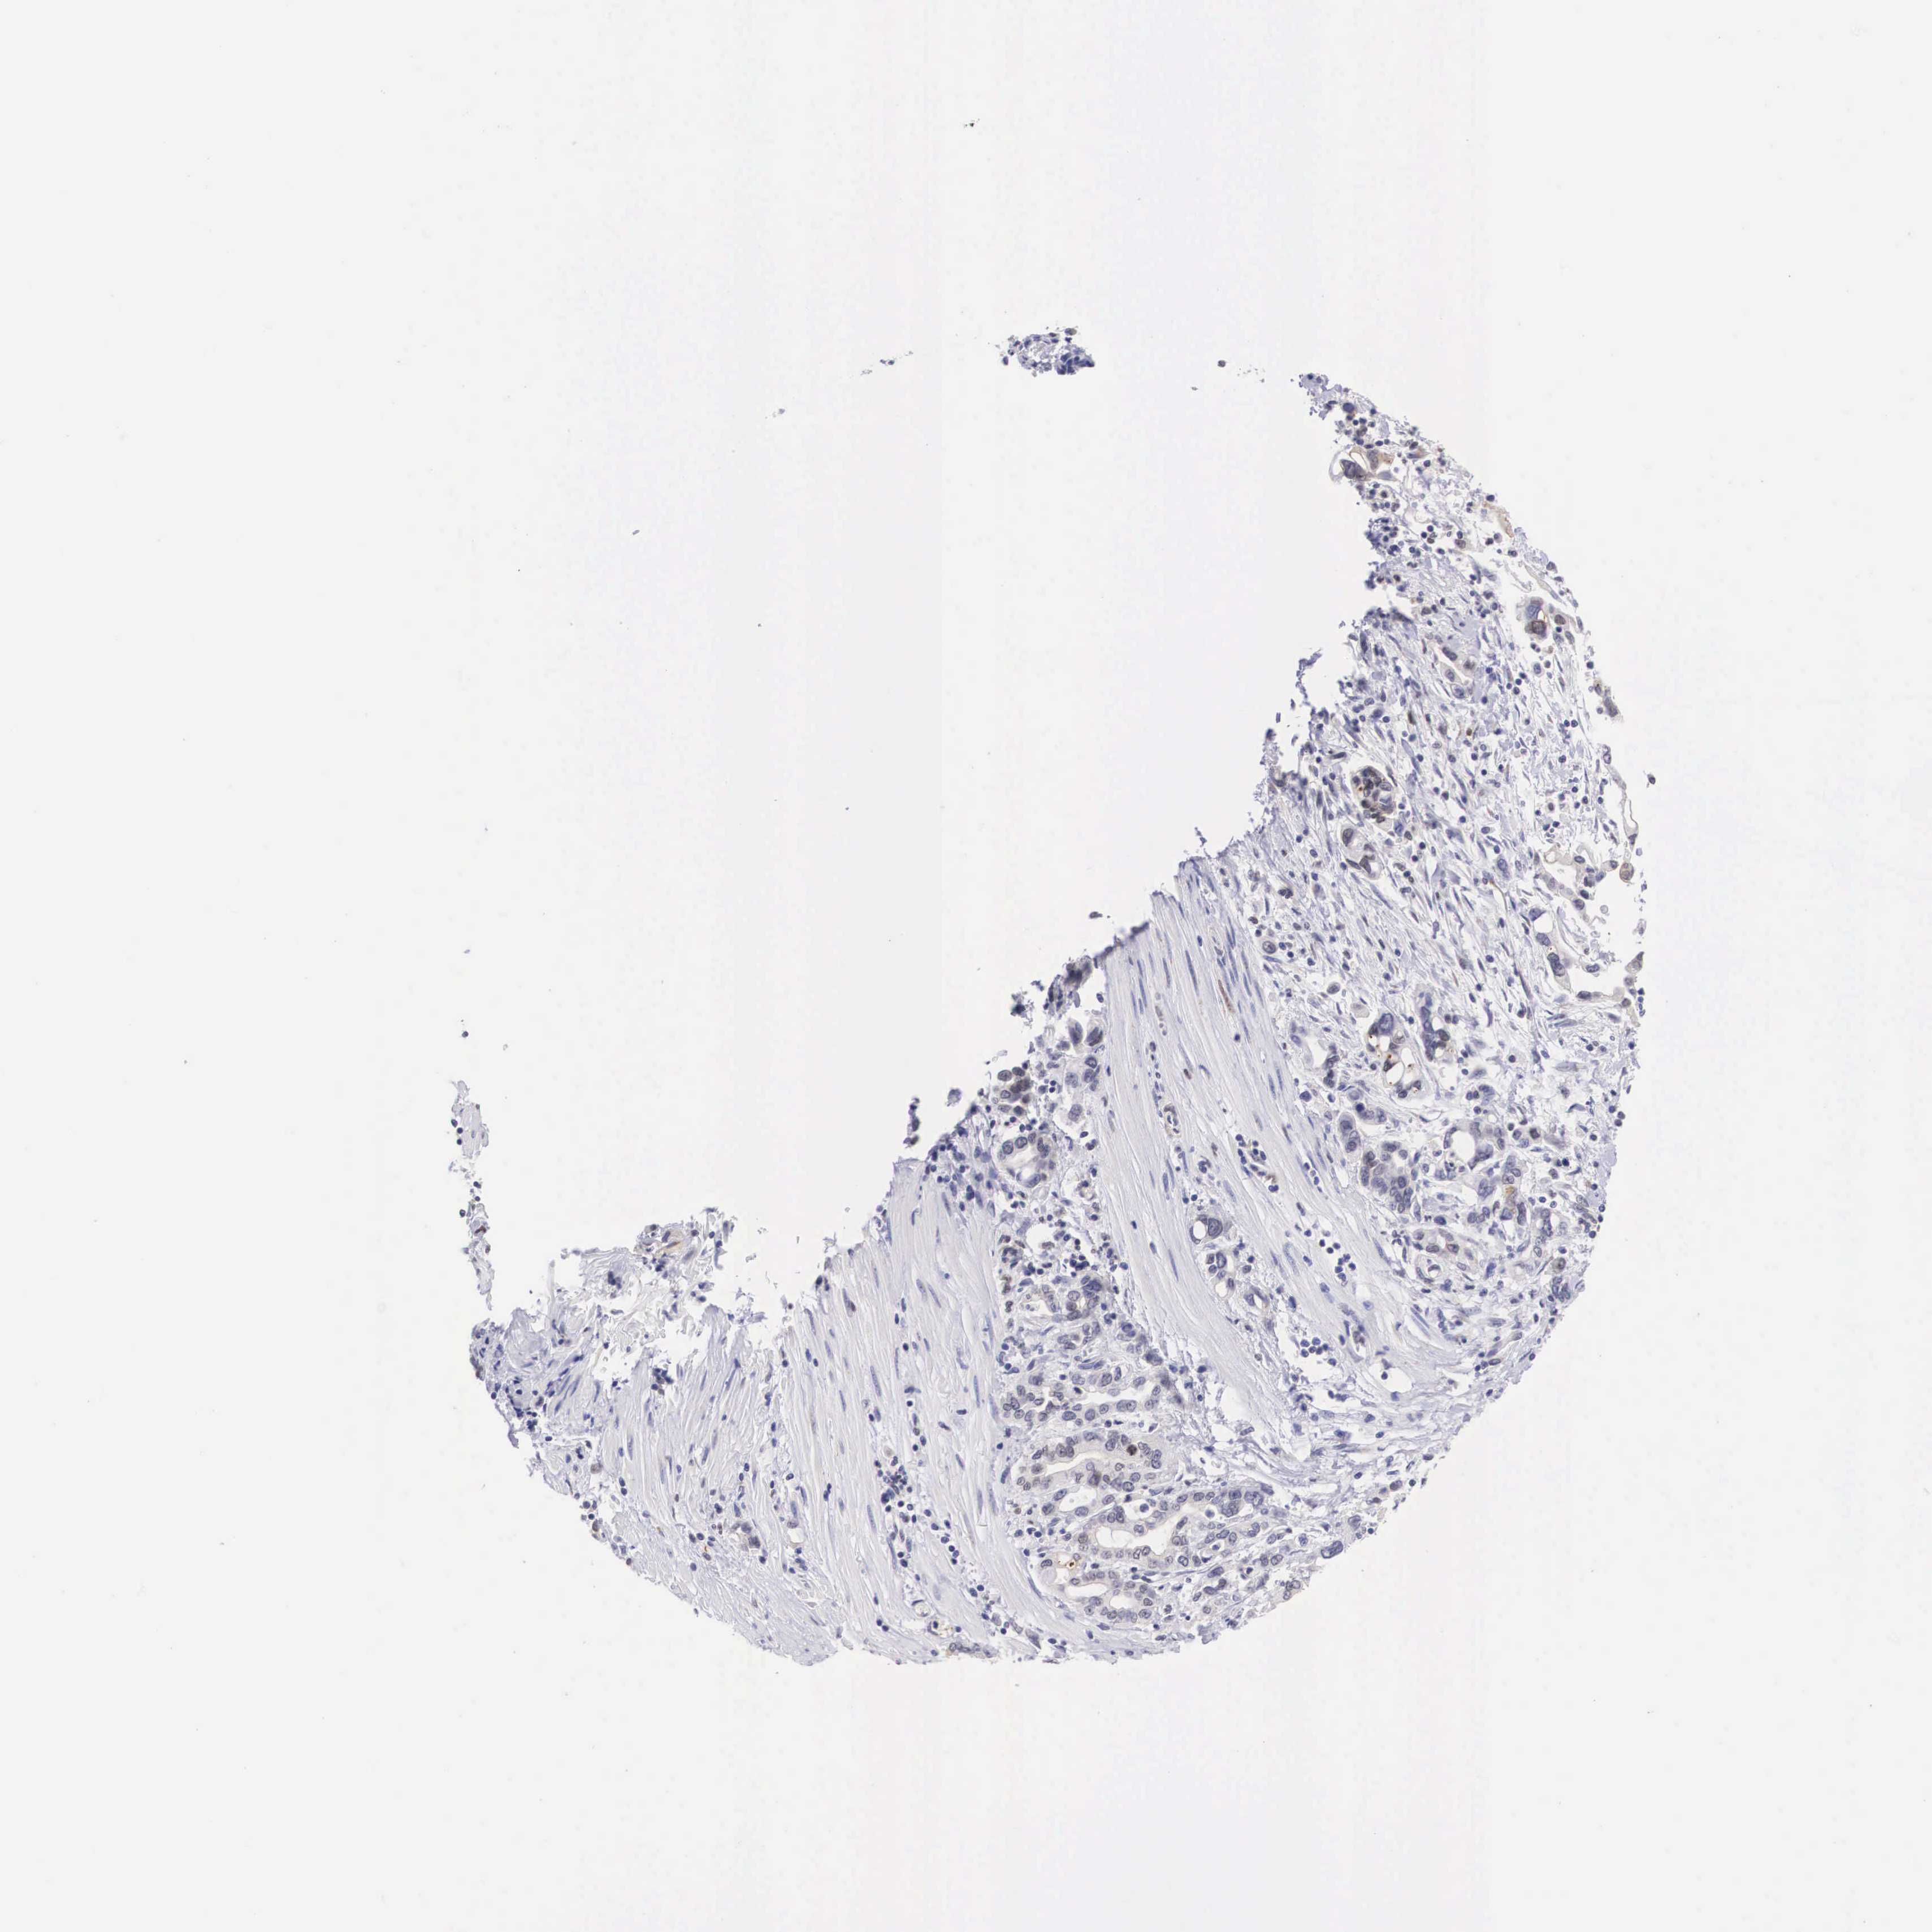

PANCREATIC CANCER - Protein expressioni

A mouse-over function shows sample information and annotation data. Click on an image to view it in a full screen mode. Samples can be filtered based on level of antibody staining by selecting one or several of the following categories: high, medium, low and not detected. The assay and annotation is described here.

Note that samples used for immunohistochemistry by the Human Protein Atlas do not correspond to samples in the TCGA dataset.

Antibody stainingi

Antibody staining in the annotated cell types in the current human tissue is reported as not detected, low, medium, or high, based on conventional immunohistochemistry profiling in selected tissues. This score is based on the combination of the staining intensity and fraction of stained cells.

Each image is clickable and will lead to virtual microscopy that enables deeper exploration of all samples and also displays staining intensity scores, fraction scores and subcellular localization as well as patient and tissue information for each sample.

Antibody HPA000264

Staining

High

Medium

Low

Not detected

Intensity

Strong

Moderate

Weak

Negative

Quantity

>75%

75%-25%

<25%

None

Location

Nuclear

Cytoplasmic/membranous

Cytoplasmic/membranous,nuclear

Adenocarcinoma, NOS